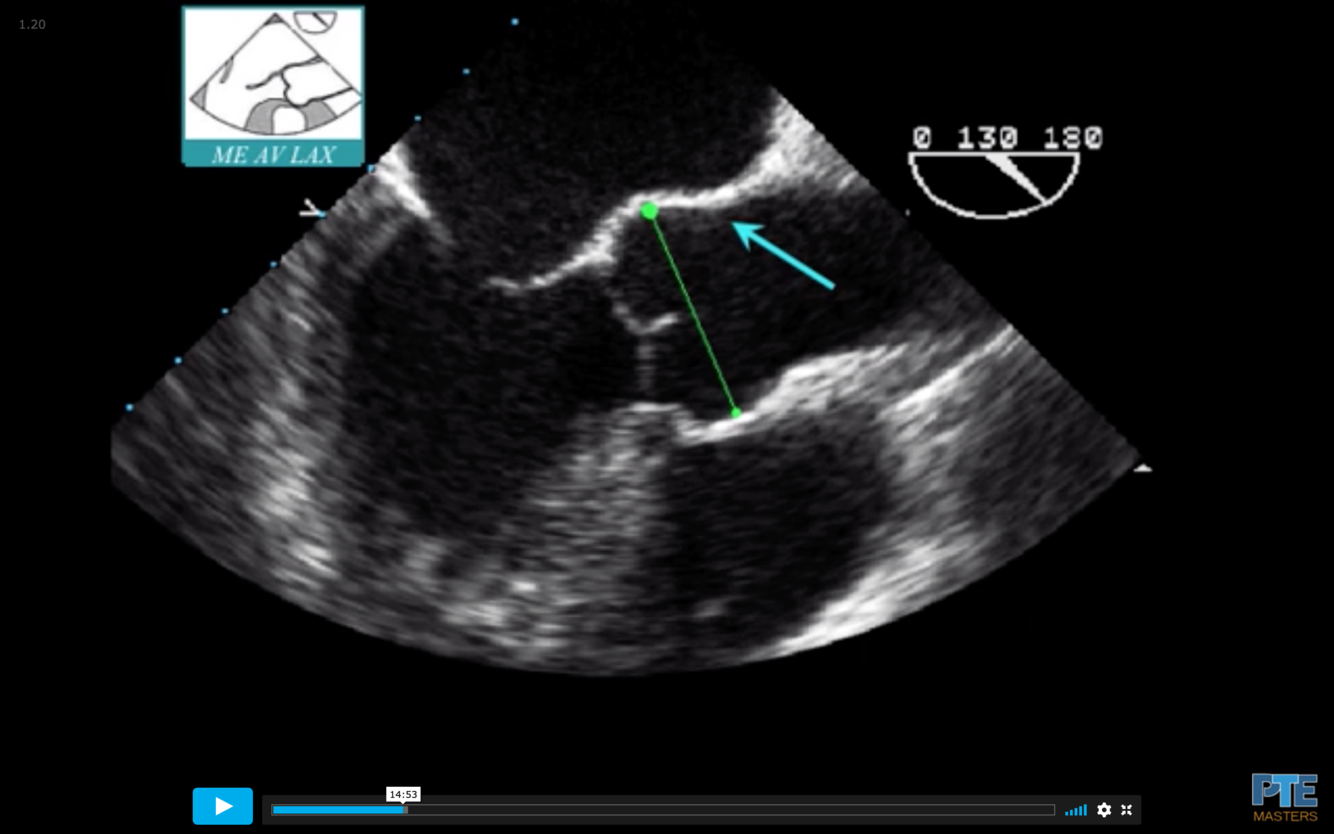

Junction in Teal

Find the ME AV LAX (120°)

Withdraw the probe to bring the right pulmonary artery in view

Decrease omniplane angle slightly by 10-20° to make the aortic wall symmetric